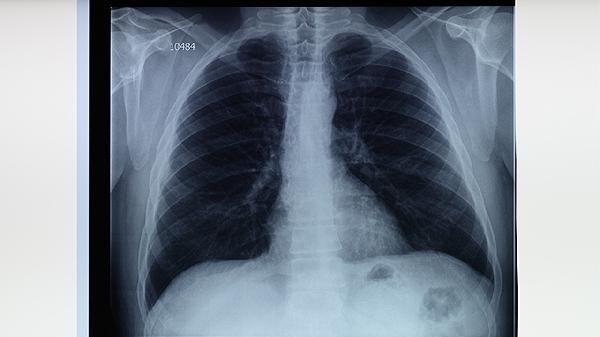

益肺清化膏可用于肺热阴虚型肺结节的辅助治疗。肺结节可能与环境粉尘刺激、长期吸烟等因素有关,通常表现为干咳少痰、咽干鼻燥等症状。肺结节患者在医生指导下可配合使用益肺清化膏,同时建议定期复查胸部CT观察结节变化。